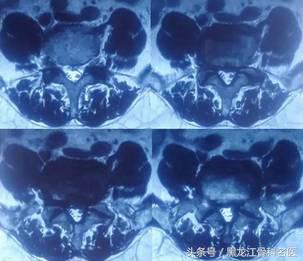

术前影像资料